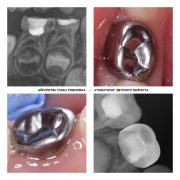

ведущий специалист по восстановлению молочных зубов коронками и лечению под наркозом.

2017г. — Обучение «Дентальная травматология в детской стоматологии или травмы временных зубов. Восстановление временных зубов коронками»